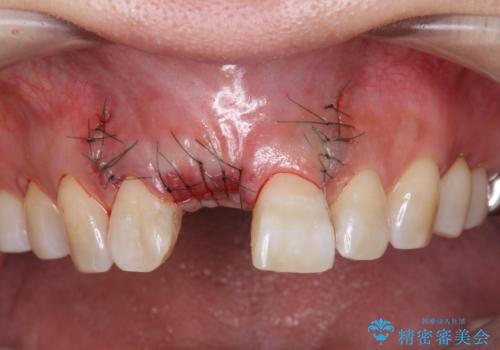

審美的・機能的に良好な位置に埋入するには、骨量が十分ではなかったため骨の造成を併用したインプラント埋入外科手術を行います。

前歯のインプラントを審美的に仕上げるには、インプラント周囲に十分な骨の量と厚みのある歯肉、そして埋入位置の精密な位置付けが重要です。